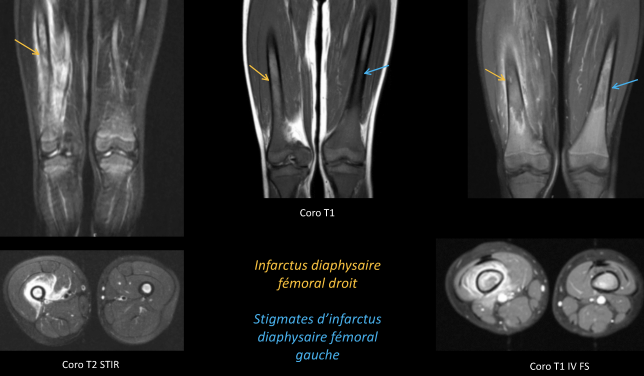

Ostéo-articulaire

- Peristance de moelle rouge dans les os longs

- Crises vaso-occlusives (Infarctus osseux, souvent multiples, l’hypersignal T1 spontané est spécifique pour le DD avec ostéomyélite)